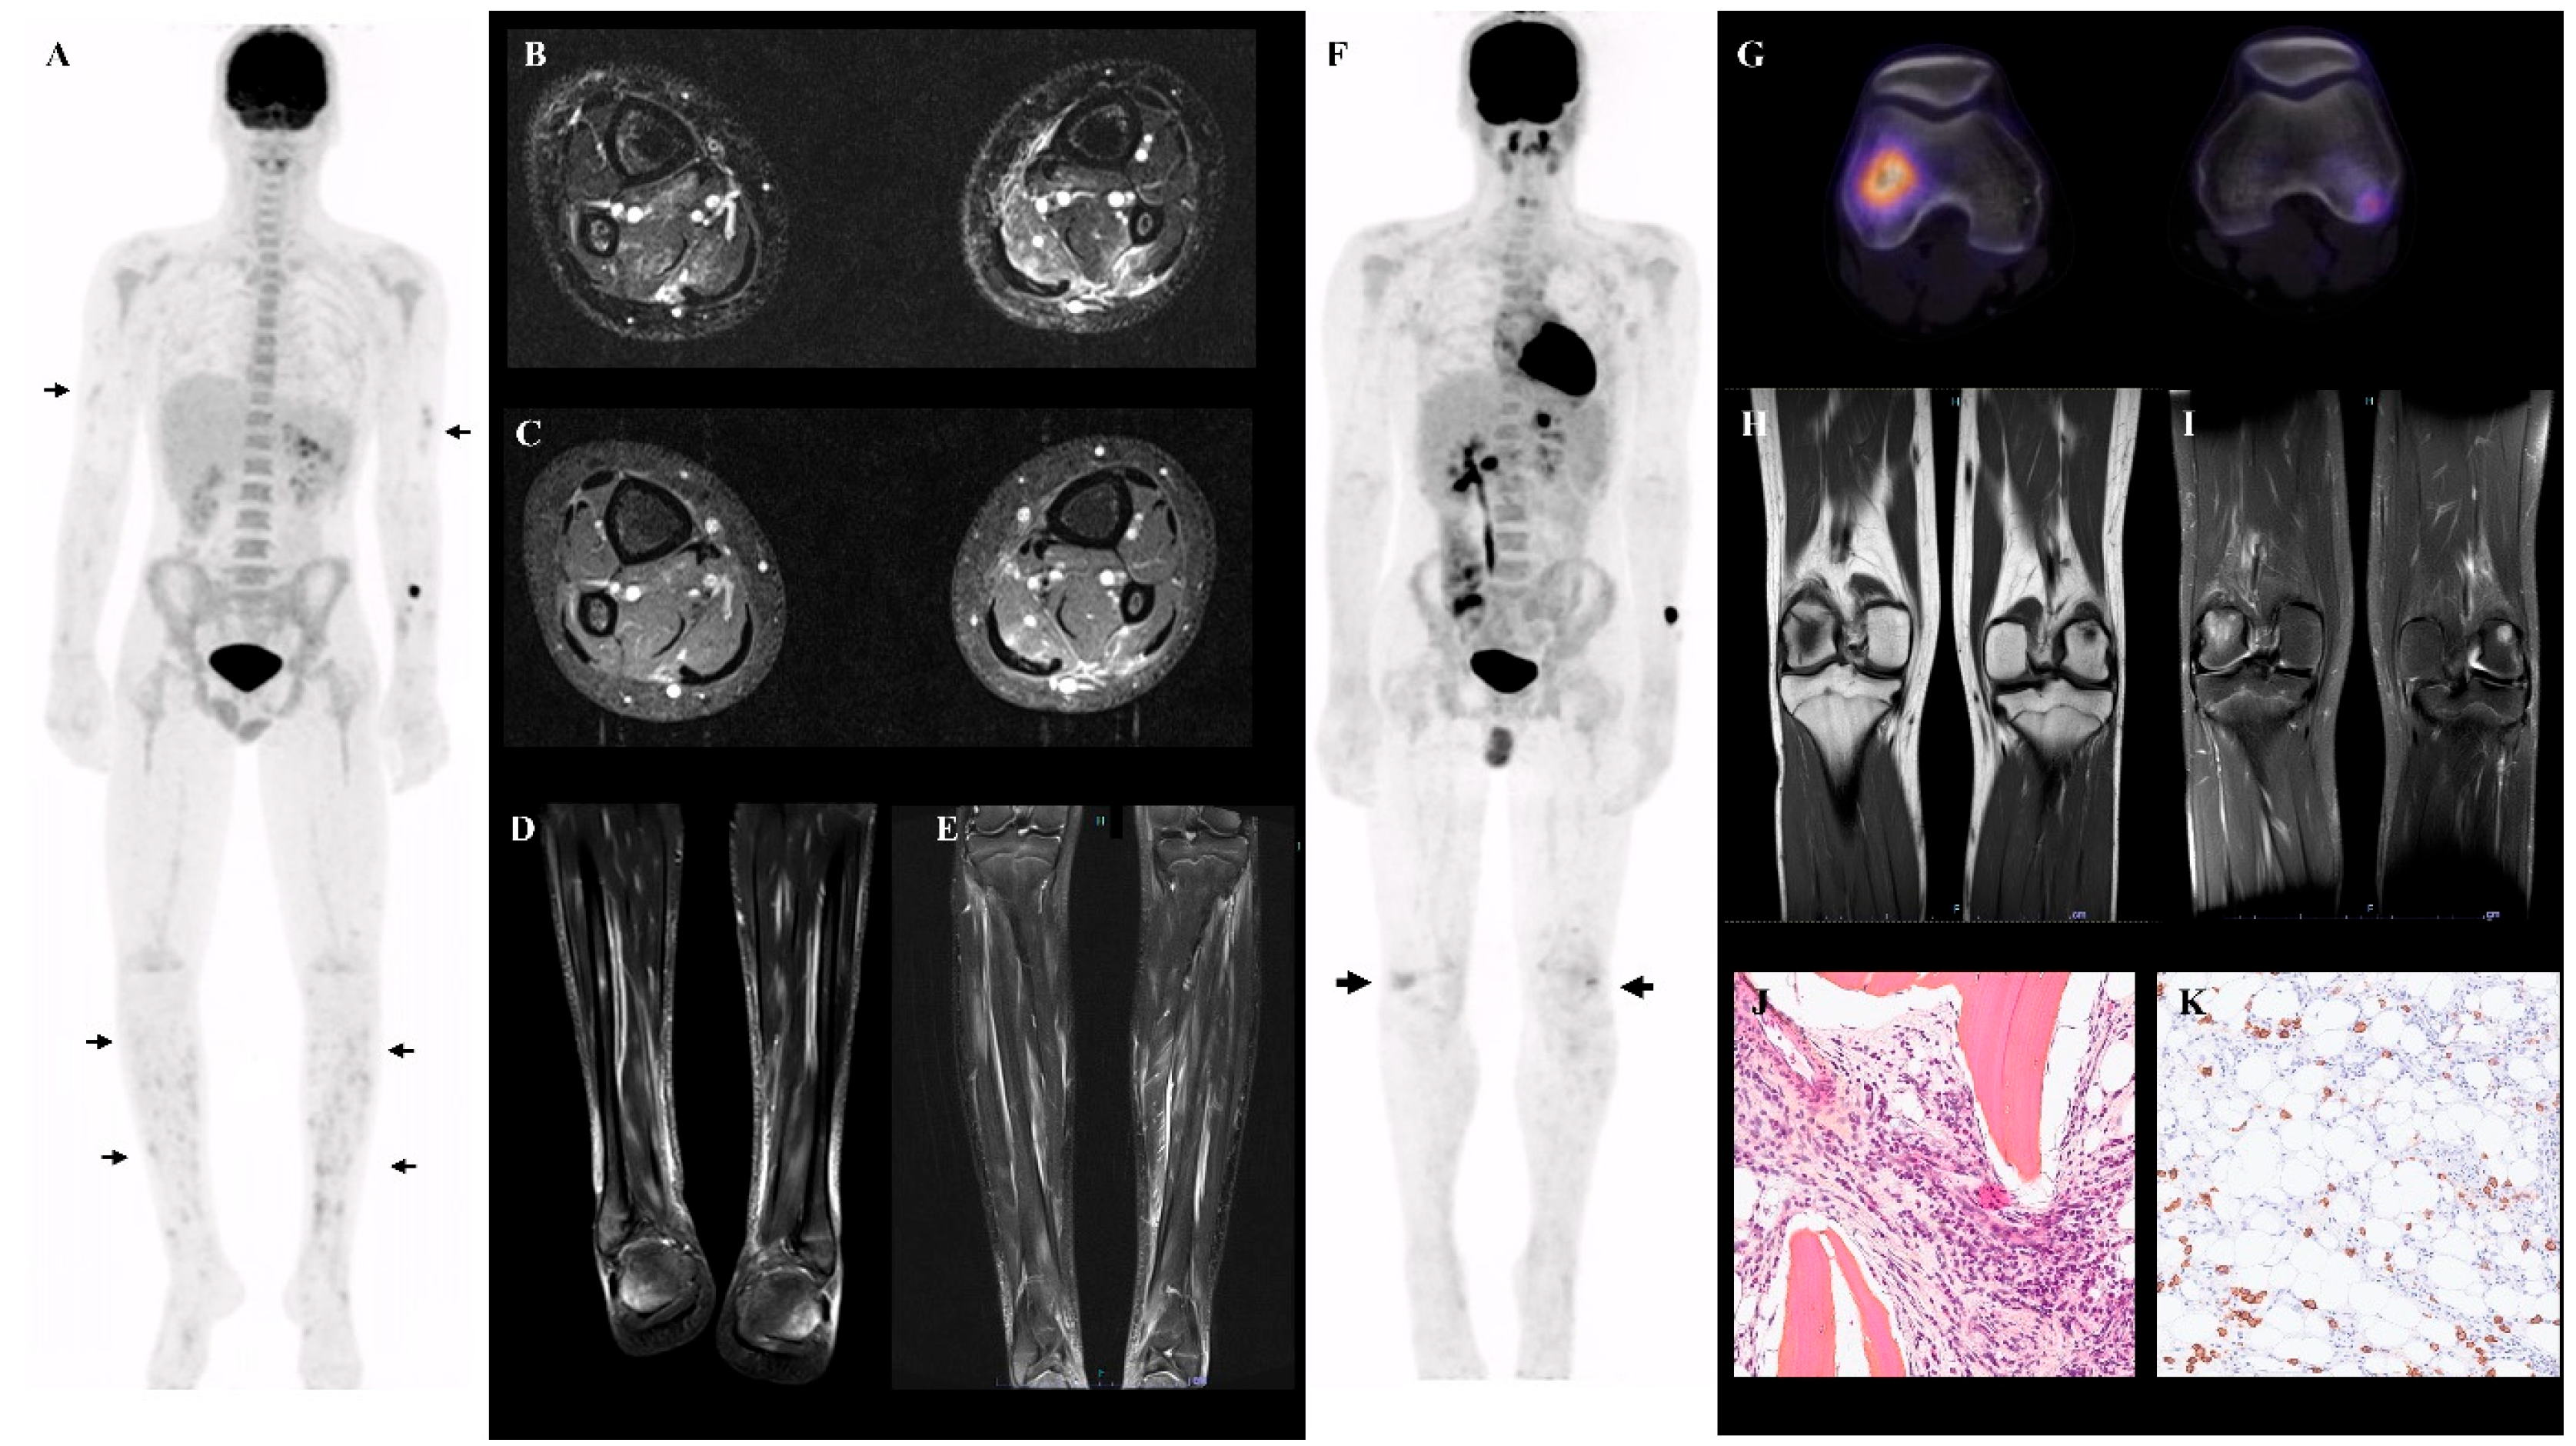

3.2. PET-CT (±MRI) Findings in Juvenile Onset PAN

PET-CT findings of each patient are summarized in Table 1. We found focal heterogeneous muscular FDG uptake in 4/6 patients, with a symmetric distribution (Figure 1A–G). In the same four patients, cutaneous/subcutaneous hypermetabolic foci were also present (Figure 1G). These findings were predominant in the muscles and skin of the lower legs. When numerous, a combination of these abnormalities can result in the so-called ‘leopard skin’ sign (Figure 1A). The intensity of the muscular and cutaneous/subcutaneous hypermetabolism was moderate (SUVmax ranging from 2.2 to 4.7). In addition, increased FDG uptake in large vessels (brachial arteries) was found in 1/6 patients (Figure 1C).

Figure 1. (A,B) Maximal intensity projection (MIP) (A) and representative fused FDG PET-CT coronal view (B) of patient 1, showing diffuse hypermetabolic foci in the lower limbs. (C) MIP FDG PET-CT of patient 2, showing diffuse hypermetabolic foci in the lower limbs, vascular uptake in both brachial arteries (black arrowhead), and the right popliteal region. (DG) Fused FDG PET-CT transverse views showing foci of increased muscular and subcutaneous FDG uptake in patients 1 and 2 (levels of the cross-sectional views are shown by black arrows in (A,C)).

We also found nonspecific, inflammation-related findings: hypermetabolic lymphadenopathies in 4/6 and splenic/medullary/thymic hypermetabolism in 6/6 (Figure 1B). These were the only abnormalities present in 2/6 patients. We found no association between clinical or biological features and PET-CT patterns.